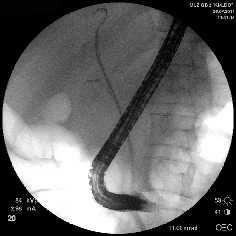

Рубцовая стриктура средней трети холедоха, холедохолитиаз

Полный блок средней трети холедоха (клипса на холедохе)

Несостоятельность культи пузырного протока

Рис. 1. Рентген-фото выявленной патологии

Rg-фото. Бужирование стриктуры холедоха

Rg-фото. Баллонная дилятация стриктуры холедоха

Rg-фото. Стентирование холедоха

Рис. 2. Наиболее часто выполняемые эндоскопические вмешательства